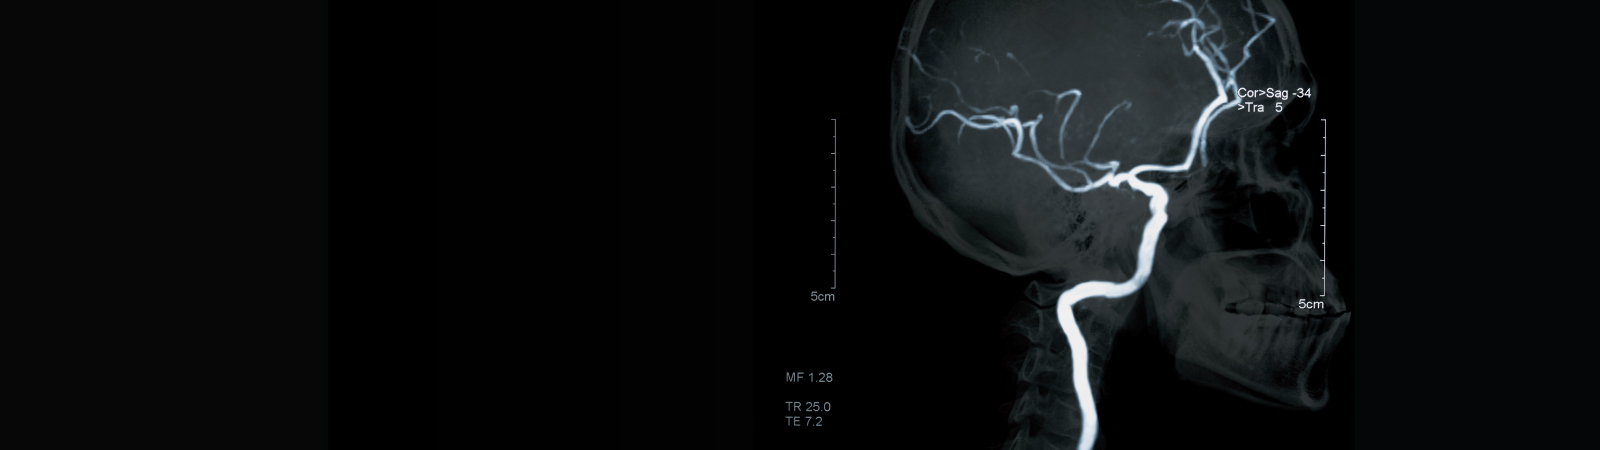

- Angiogram: An angiogram is a test that uses X-rays to check the blood vessels for damage. Dye is injected into the vessels through a catheter, allowing them to be visible on the X-rays.

- Magnetic resonance imaging (MRI): An MRI is a safe and painless test that uses radio waves and magnets to create a detailed view of the inside of the body.

- Other tests: including CT or MR angiography, or cerebrovascular reserve testing with CT or MRI.